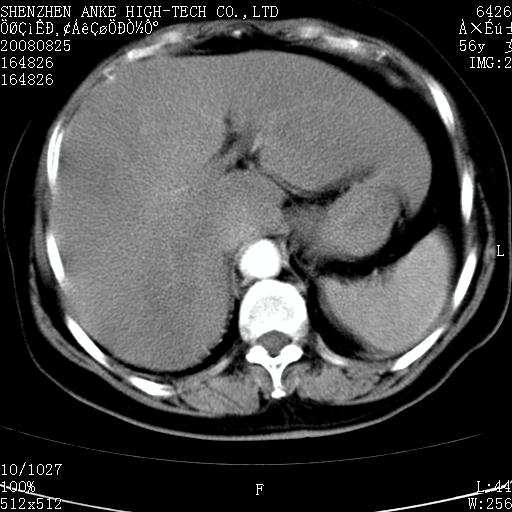

患者,女性,56岁,腰痛3年,查:右腹部约8x10cm肿块,固定,无压痛;8月23日在外院做了平扫,发现右肾巨大肿块(外院具体诊断不祥);今天在我院做了静脉肾盂造影,示:右肾明显增大,分泌功能明显减弱。

右肾癌可能大。

右肾癌

右肾癌可能性大.

右肾占位、癌可能性大。

支持右巨大肾癌。

1)考虑右肾癌并右肾静脉瘤栓形成。2)脂肪肝。

右肾癌可能性大。

右肾癌性变。

考虑右肾癌可能性。